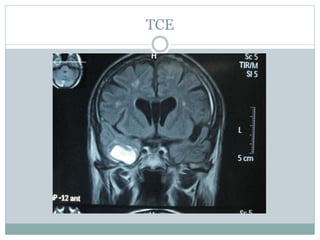

TCE